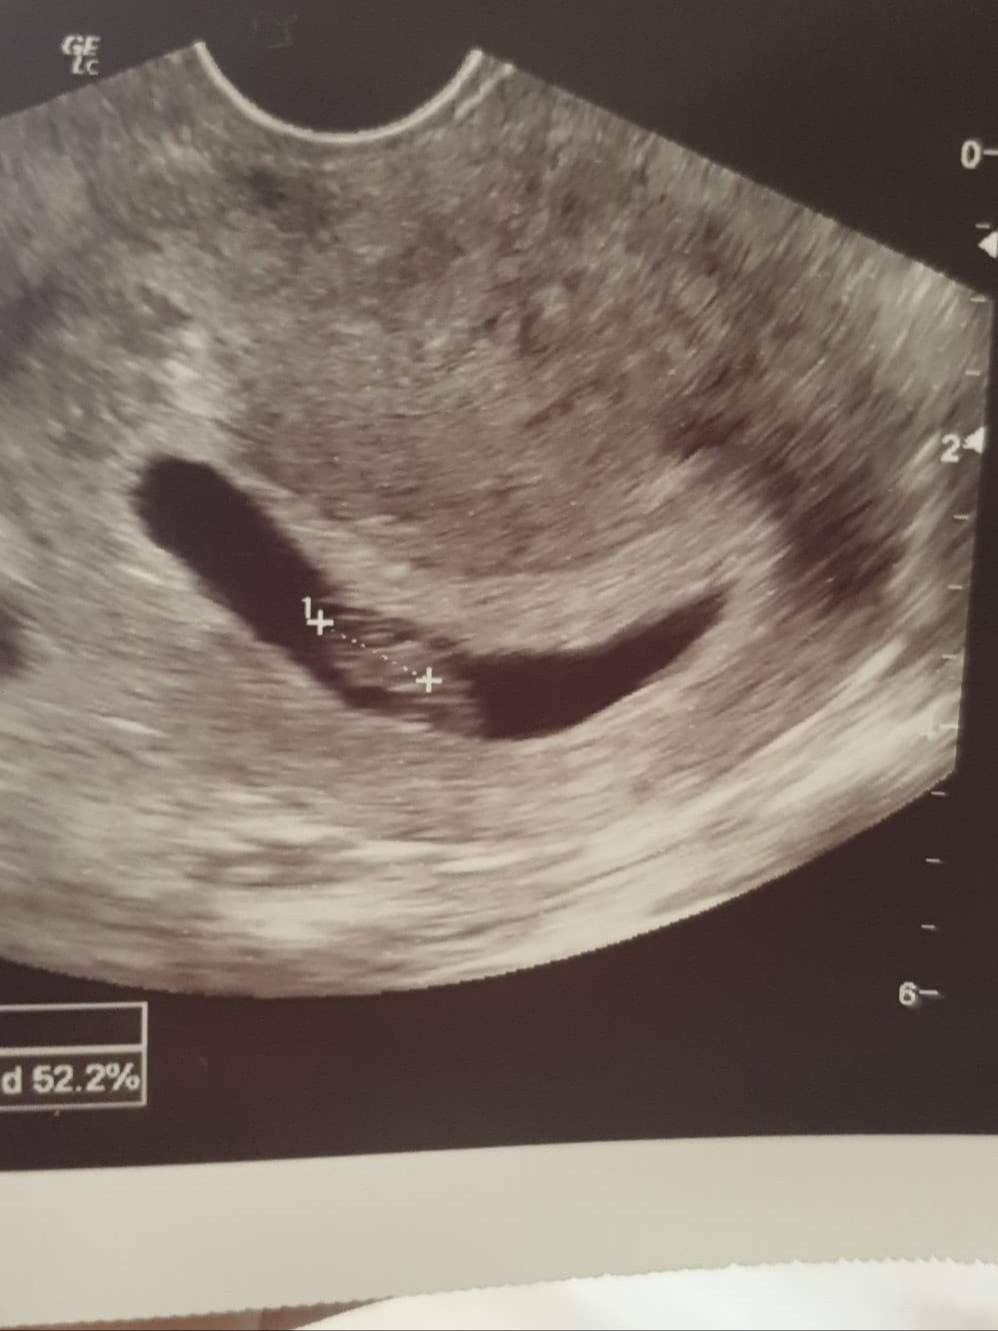

To jest moje z 7 tyg. Więc myślę, że na spokojnie. Tym bardziej, że lekarz wychwycił ☺

Jutro się wszystkiego dowiem. A objawy jakie miałaś? Ja na dzień dzisiejszy oprócz pobolewania podbrzusza, częstych wizyt w toalecie, wzdęć i czasem zgagi, czasem zaparć i lekkich jakby nudności innych nie mam. Ogólnie czuje się taka przepełniona w żołądku.To jest moje z 7 tyg. Więc myślę, że na spokojnie. Tym bardziej, że lekarz wychwycił ☺